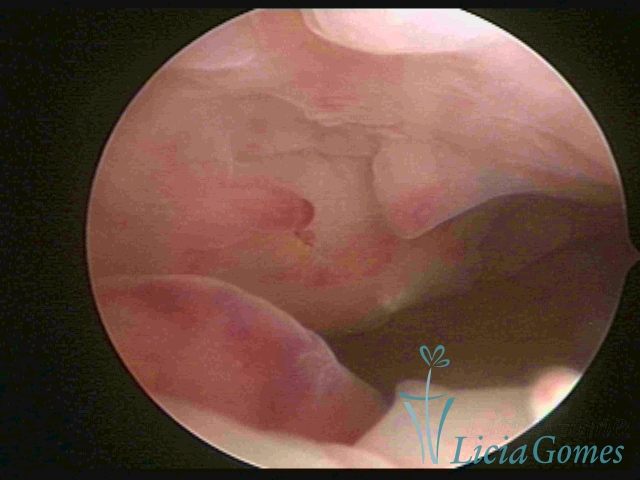

A hipertrofia polipoide é visualizada quando o crescimento endometrial é mais pronunciado, e como o espaço da cavidade uterina é limitado, forma dobras ou sulcos, simulando lesões pseudo polipoides ou polipoides.

Na hipertrofia simples há um aumento da espessura endometrial com protuberância do pontilhado glandular, diferindo do padrão endometrial proliferativo pela perda da vascularização reticular superficial. Outra forma de hiperplasia simples é a glandular cística, onde também se visualiza lesões císticas intercaladas ao endométrio hipertrófico.

A Hiperplasia Complexa tem um aspecto pseudo polipoide, lembrando tecido cerebroide ou com reação deciduoide. A vascularização superficial é mais evidente e com vasos em formatos de saca-rolha ou espirais.